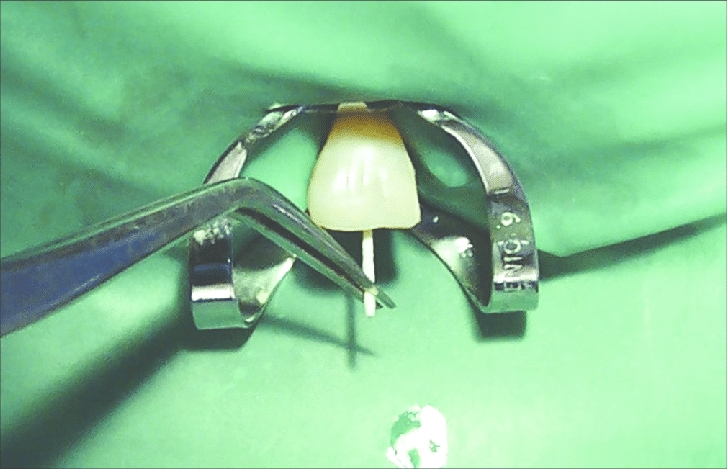

Endodontics: Gutta Percha & Paper Points.

Root Canal Treatment: Diapex Plus, Diapaste, Dia-Root Bio MTA.